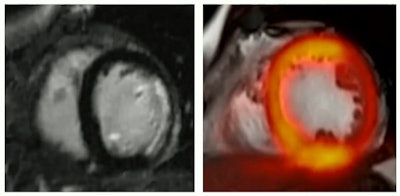

However, in compliant patients, PET/MRI can be used to diagnose acute myocardial infarction, where MRI provides late enhancement images suggesting myocardial hypometabolism and PET FDG radiotracer uptake further allows the differentiation between healthy tissue and scarring.

Hybrid late-enhancement MRI and PET imaging can help diagnose acute myocardial infarction.

Hybrid late-enhancement MRI and PET imaging can help diagnose acute myocardial infarction.PET/MRI can also be used to diagnose acute myocarditis, and in fact, in some cases has improved diagnostic confidence when infections aren't clear on MRI, she continued. This again is due to the addition of PET radiotracer uptake in the images showing active inflammation.